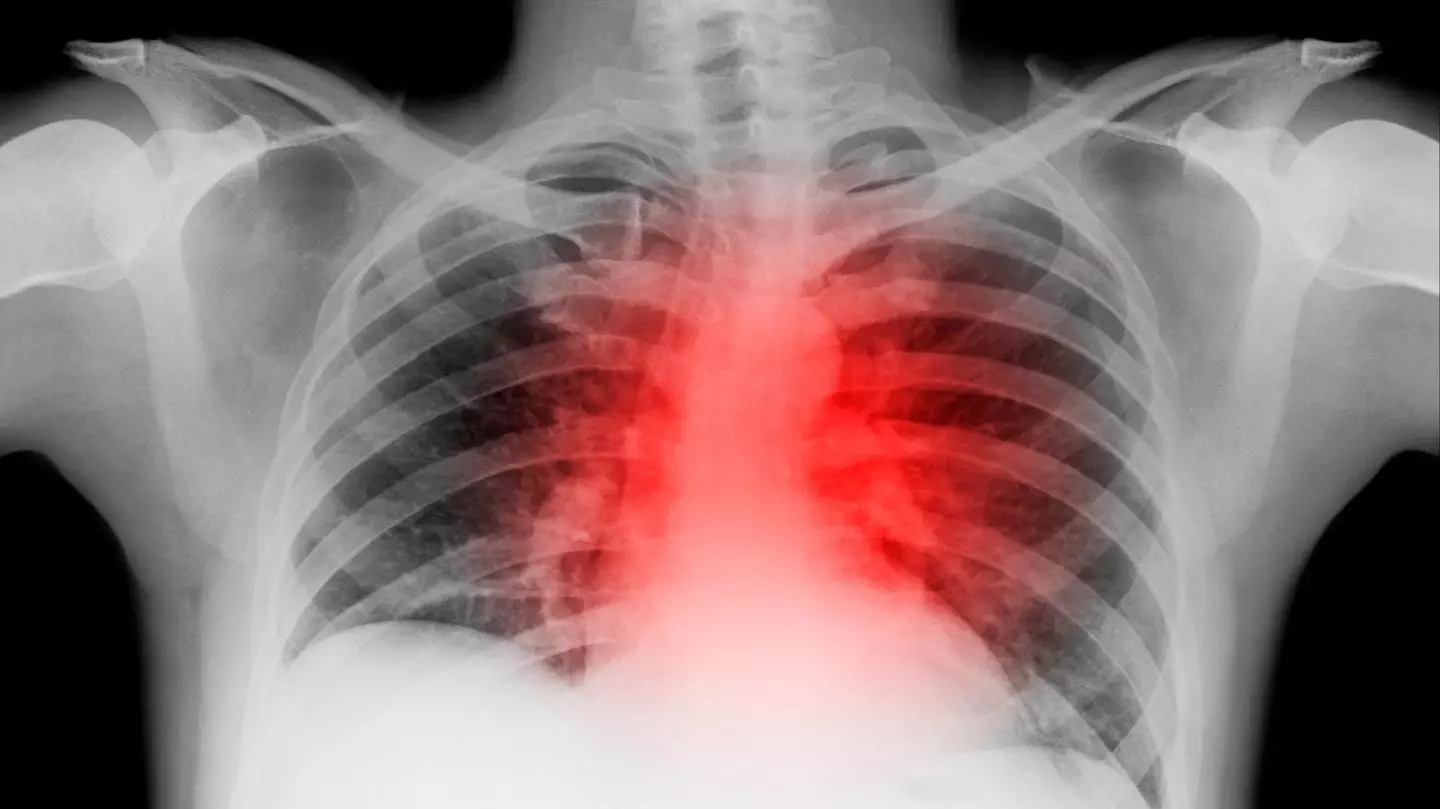

Chest pain

Chest pain is often caused by heartburn or indigestion, although sudden and persistent pain could be a sign of something dangerous.

According to the NHS, chest pain which lasts more than 15 minutes and spreads to the jaw or left arm may indicate a heart attack. Severe indigestion can also be a symptom.

Another life-threatening cause is pulmonary embolism, where a blood clot blocks blood flow to the lungs. This may lead to sharp pain worsened by coughing, shortness of breath or coughing up blood.

"Thousands of people suffer heart attacks every year and don't realise it at first," Dr Cannon said.

"Embolisms are less common, but need to be treated immediately."